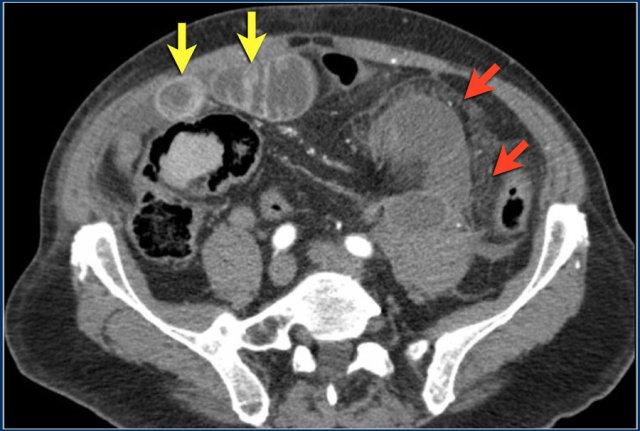

The CT-image shows nice enhancement of the normal bowel wall (yellow arrows) and no enhancement of the infarcted bowel (red arrows).

This would not be visible if positive oral contrast was given.